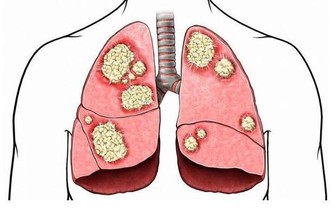

天氣熱的時候,心火比較旺,心火旺會造成腎水虛衰和肺金虛衰,因此,夏天還要清心火、補肺養腎。